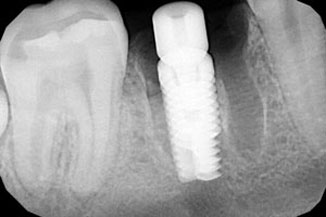

Качество снимков обладает высокой разрешающей способностью отношение сигнал /шум – важнейший фактор в получении изображения, составляет >37 dB, размер пикселя 0,035 мм. Благодаря высокой чувствительности и вариабельности размеров датчиков, визуализация становится детальной, в этой связи возможно проведение диагностики кариеса на контактных поверхностях. Преимущества данной методики при сравнении с пленочной рентгенографии состоит в скорости получения изображения объекта исследования, низкая доза облучения пациентов, возможность постпроцессорской обработки, визуализации деталей в диагностике послеоперационных результатов дентальной имплантации, эндодонтического лечения и постэндодонтического лечения (Рис.5), уточнения расположения кист, гранулем, конкрементов в протоках слюнных желез.

Рис. 5 Диагностика дентальной имплантации и эндодонтичского лечения.